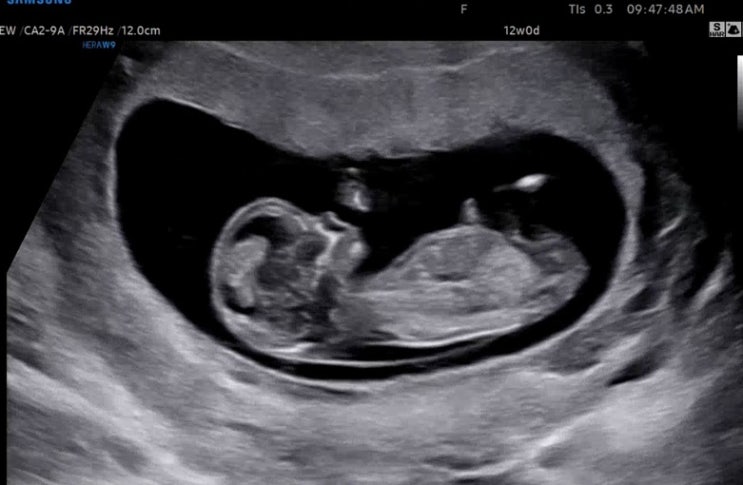

임신 12주 1차 기형아 검사 초음파 결과, 1차 기형아검사 성별

임신의 안정기라 불리는 임신 12주차에 진입한 래용? 입덧은 잔잔히 계속되고 있지만 래용이가 안정기에...